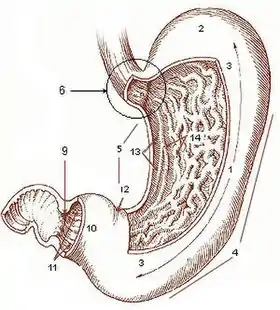

Diagram from cancer.gov: Rugae can be seen within stomach. | |

In anatomy, rugae are a series of ridges produced by folding of the wall of an organ.[1] Most commonly rugae refers to the gastric rugae of the internal surface of the stomach.

A purpose of the gastric rugae is to allow for expansion of the stomach after the consumption of foods and liquids. This expansion increases the volume of the stomach to hold larger amounts of food. The folds also result in greater surface area, allowing the stomach to absorb nutrients more quickly.

With few exceptions (e.g. the scrotum), rugae are only evident when an organ or tissue is deflated or relaxed. For example, rugae are evident within the stomach when it is deflated. However, when the stomach distends, the rugae unfold to allow for the increase in volume. On the other hand, plicae remain folded regardless of distension as is evident within the plicae of the small intestine walls.